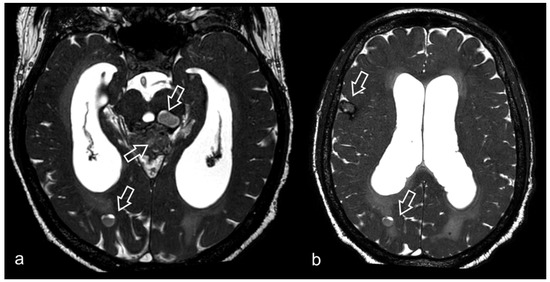

3.2. Virchow–Robin Spaces

3.6. Neurocysticercosis